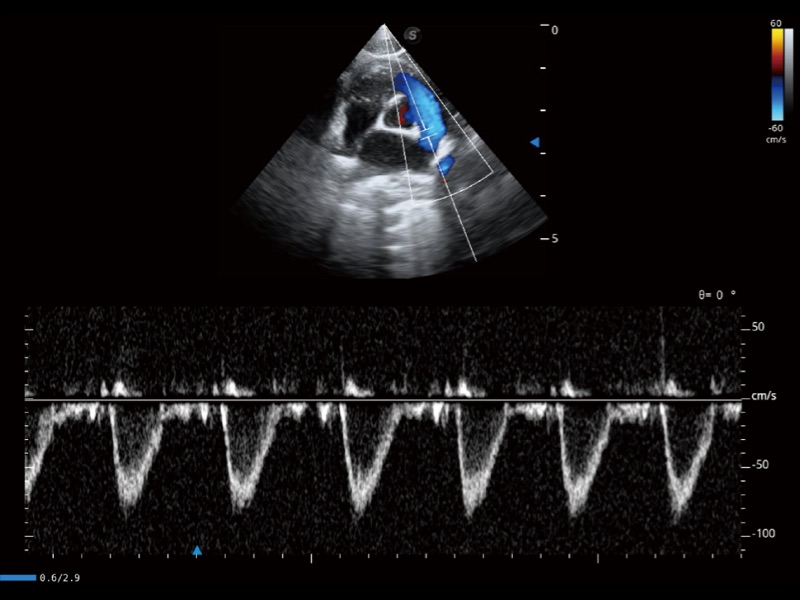

(犬)左室长轴血流